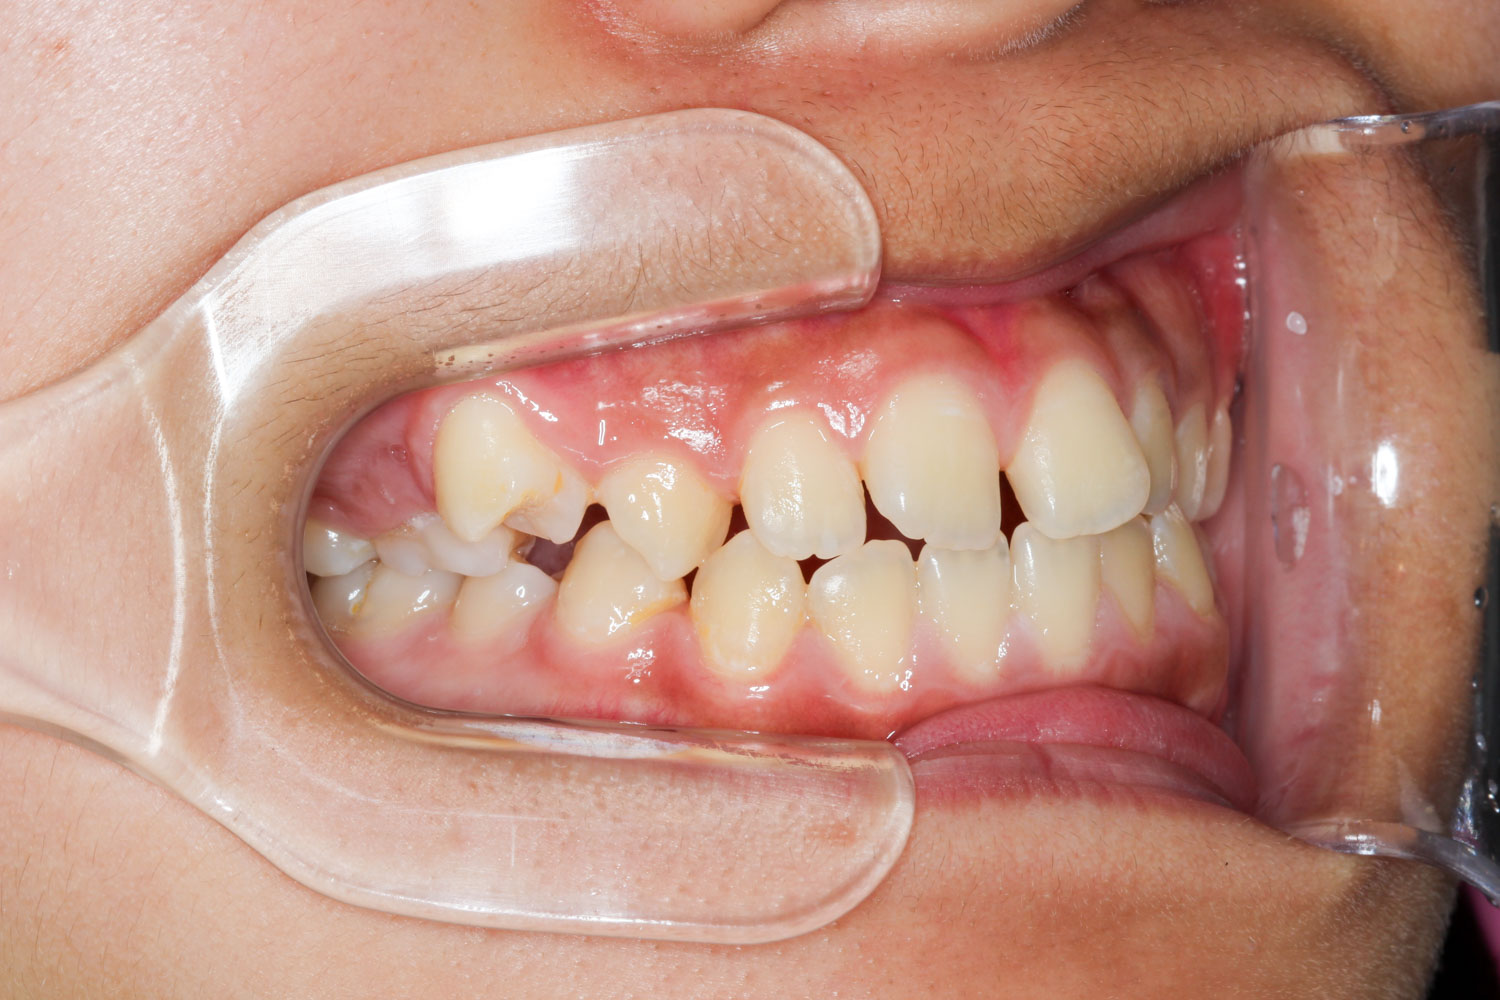

Before

年齢 10代

治療装置 表側の矯正装置(ホワイトコース)

治療内容 上下左右4本抜歯

治療期間 2年1か月

リスク 歯の移動に伴う痛み、歯肉退縮、歯根吸収、歯肉炎、虫歯

主訴 ガタガタが気になる

症状 叢生(ガタガタ)

治療回数 25回程度

総額費用 105万円程度